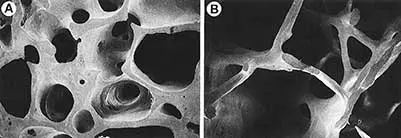

Okres okołomenopauzalny, który obejmuje kilka lat poprzedzających menopauzę oraz co najmniej 12 miesięcy po menopauzie, wiąże się z ustaniem ochronnego działania estrogenów na tkankę kostną, polegającego na stymulowaniu osteogenezy i hamowaniu procesu resorpcji kości [1, 7]. W okresie pomenopauzalnym występuje osteoporoza pierwotna inwolucyjna, której cechą charakterystyczną jest utrata warstwy beleczkowej kości w stosunku do warstwy zbitej, a zmniejszenie masy kostnej spowodowane jest przez nadmierną aktywność komórek kościogubnych [1, 2].

Obraz prawidłowej tkanki kostnej gąbczastej oraz tkanki dotkniętej osteoporozą przedstawia rycina 1. Kość osoby chorej ma nie tylko mniejszą masę kostną, ale również zmienioną strukturę [8].

Ryc. 1. Obrazy z elektronowego mikroskopu skaningowego kości gąbczastej z grzebienia biodrowego u osoby ze zdrowym kośćcem (A) oraz chorej na osteoporozę (B) (źródło [8])